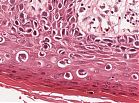

A100 M. Paget der Mamille

Epidermis mit Tumorinfiltraten basal und pagetoid (hohe Vergrößerung)

A100 M. Paget der Mamille

Tumorzellnester basal und Tumoreinzelzellen, die in bis in das Stratum corneum aufsteigen.